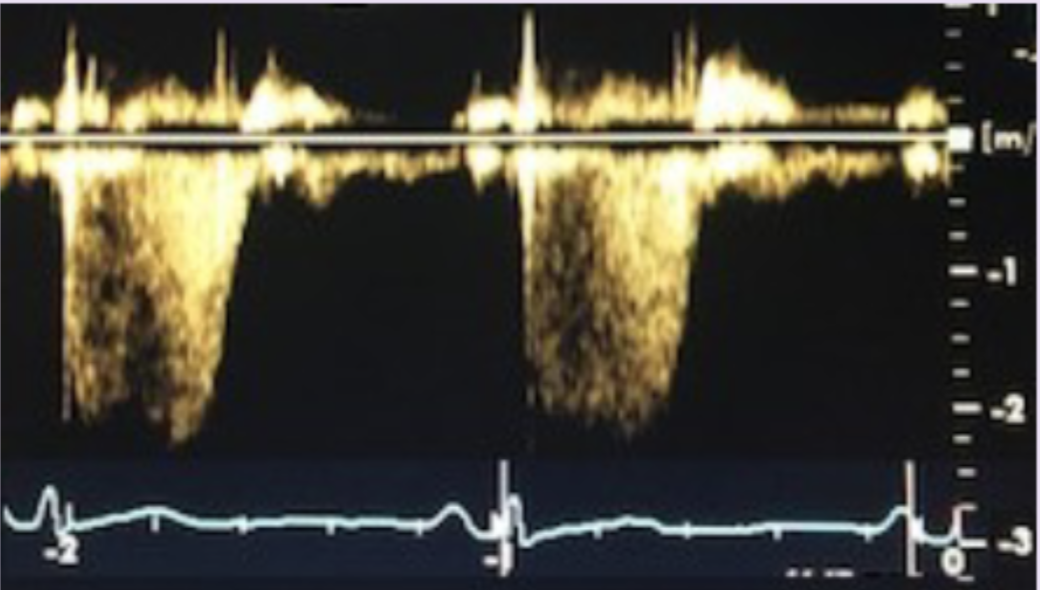

What waveform is this and is it PW or CW?

22